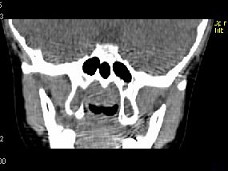

4.女,8歲,頭痛,鼻塞半年余,CT如圖所示,最可能診斷為  (    )

正確答案:C